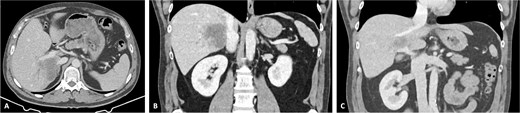

The post-operative period was complicated by bleeding from the left epigastric artery at the APFP harvesting site on post-operative day 14, requiring reintervention and vessel ligation. The patient was discharged on post-operative day 31. Pathology confirmed an ypT4G2N1R0 small-duct intrahepatic cholangiocarcinoma. No post-operative thrombosis or clinically significant stenosis were identified. Figure 6 demonstrates the reconstructed vessels 1 year after surgery. After completing 6 weeks of therapeutic low-molecular-weight heparin (LMWH), the patient continued rivaroxaban 20 mg once daily.

Reconstructed IVC and PV. (A) IVC and (B) PV 1 year after surgery.